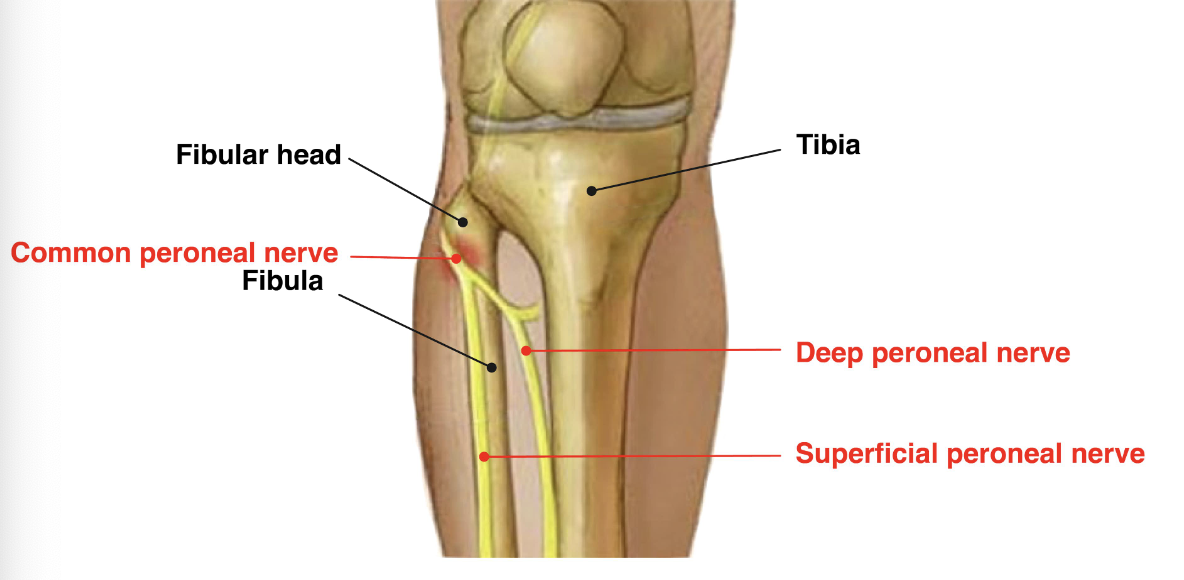

branches of the common peroneal n

A

deep peroneal n

superficial peroneal n

How well did you know this?

1

damage to the common peroneal nerve happens with injury at the

proximal fibula (fibular head)

2 PE findings of damage to the common peroneal nerve

foot drop

numbness in web space btw 1st/2nd toes

Not at all

2

3

4

5

Perfectly

13

Q

sensory and motor fxn of the deep peroneal n

sensory: first and second toe

motor: tibialis anterior -> foot dorsiflexion/inversion, great toe extension

14

sensory and motor fxn of the superficial peroneal n

motor: ankle eversion

sensory: dorsum of foot

15

what nerve controls plantar flexion of the ankle

tibial

16

2 rf for common peroneal n injury

leg cast

prolonged lying